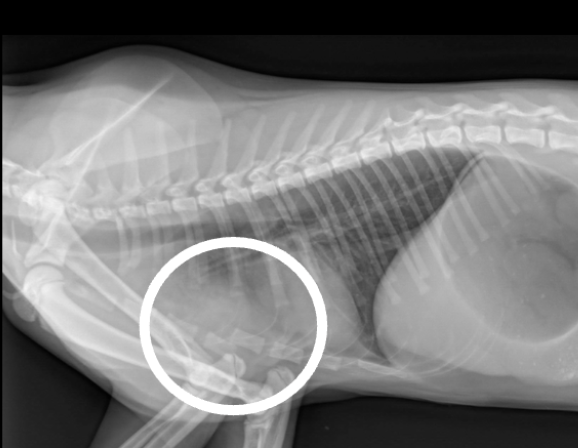

Radiographs at the primary clinic revealed an unstructured interstitial lung pattern in the cranial ventral lung lobes and sternal subluxation, suggesting concurrent thoracic trauma. Boris was then referred to a specialty facility for further management.

Figure 1. Unstructured interstitial pattern in the cranial lung fields suggestive of pulmonary contusions as well as sternal subluxation. The image was obtained by a primary veterinarian prior to the referral.